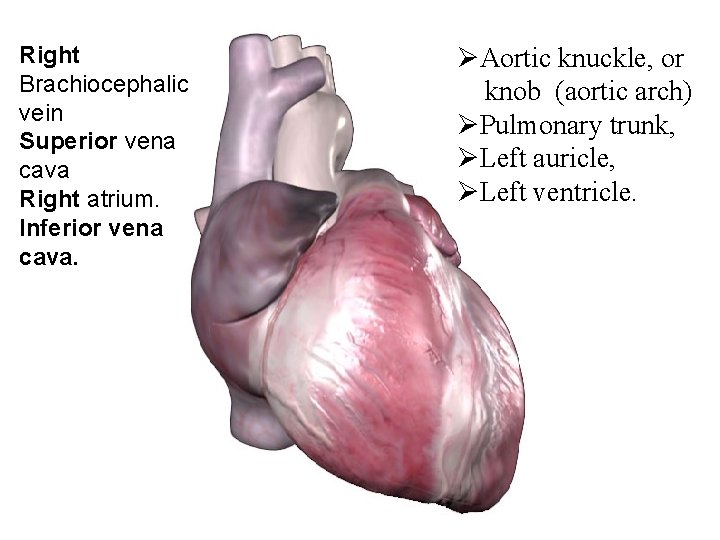

Right Brachiocephalic vein Superior vena cava Right atrium. Inferior vena cava. ØAortic knuckle, or knob (aortic arch) ØPulmonary trunk, ØLeft auricle, ØLeft ventricle.